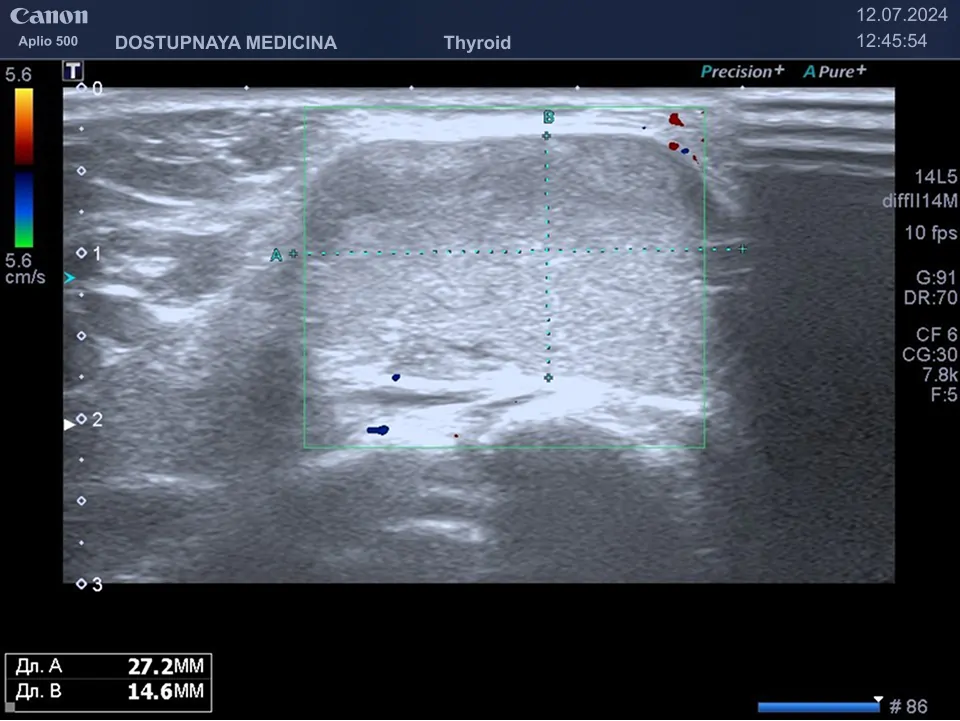

Клинический пример №2: Липома в области шеи